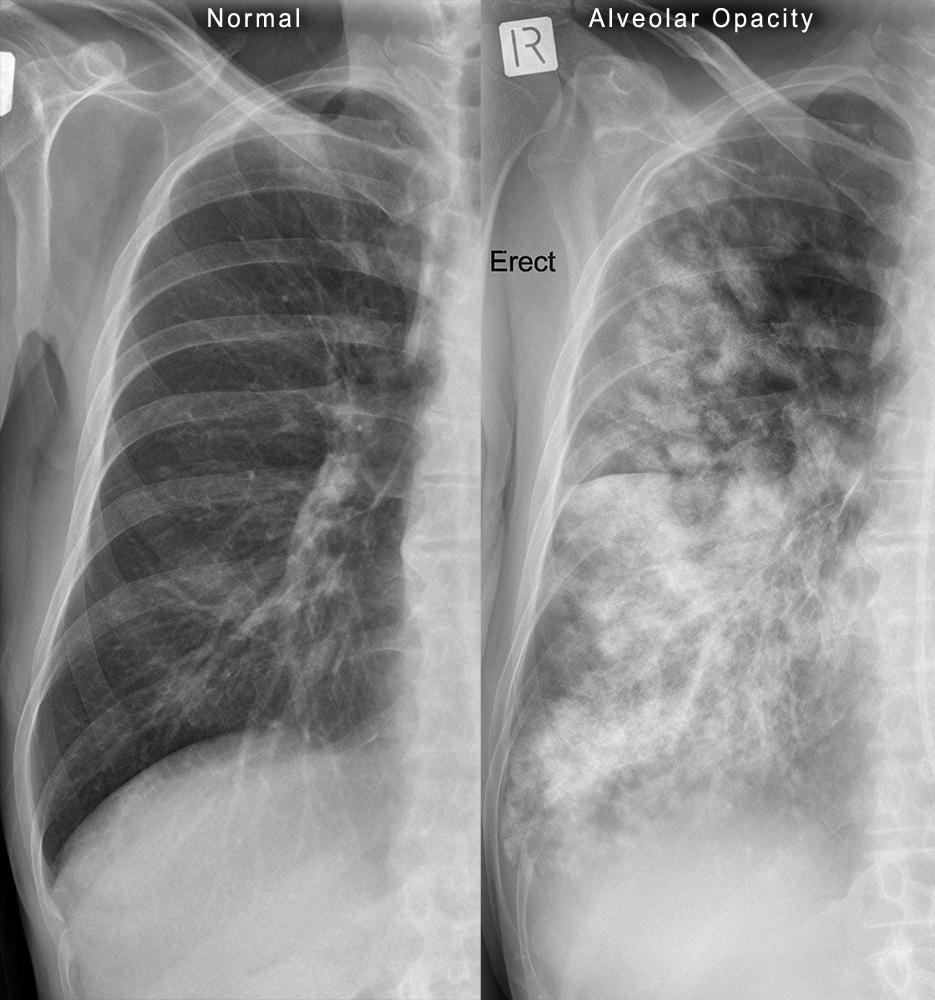

Fine reticular opacities are reliable evidence of interstitial lung disease that requires consideration of a variety of acute and chronic diseases. Acute interstitial disease is most often the result of interstitial edema or pneumonia. Both may spread through the bronchovascular and septal interstitium. Involvement of the interlobular septa in the periphery of the lung are described as Kerley B lines. Kerley B lines are a common finding in patients with interstitial edema, but when they are more chronic they are a clue to suspect lymphangitic spread of a tumor. The collagen vascular and idiopathic interstitial lung diseases cause interstitial scarring that is more disorganized and does not spare the normal interstitial septa. Fine reticular opacities may be evidence of an early stage of these diseases.

The diffuse, fine reticular pattern (see Fig. 18.1 ) is one of the most reliable patterns for identifying diffuse interstitial disease. Because this pattern is linear, the lines must be distinguished from the normal pattern of blood vessels. In the early stages of an interstitial disease, this may be impossible by chest radiography, and high-resolution computed tomography (HRCT) may be required to confirm minimal interstitial disease. Interstitial diseases may spread throughout the bronchovascular or the septal interstitium while fibrotic diseases destroy the normal lung tissues, but both processes cause fine reticular opacities.

Kerley lines are the most reliable radiologic observation for making the distinction of bronchovascular versus septal interstitial disease. 150 , 175 , 235 Kerley B lines are short lines that are perpendicular to the pleura and continuous with it. The latter feature distinguishes the Kerley B lines from small vessels. Kerley B lines are usually observed in the costophrenic angles on the posteroanterior view and, occasionally, on the lateral view in the retrosternal clear space. They were first thought to represent only enlarged lymphatics but, based on pathologic correlations, these lines represent more generalized, enlarged interlobular septa. (Answer to question 1 is a .) Although it is true that the engorgement of septal lymphatic vessels would contribute to Kerley B lines, this has probably been overemphasized. In lymphangitic carcinomatosis, metastatic tumor spreads through dilated lymphatics in the interlobular septa and causes fine reticular opacities. In the other entities listed in Chart 18.1 , dilation of lymphatics is not a sufficient explanation for the presence of Kerley B lines. Furthermore, in congestive heart failure, edema of the loose connective tissue of the interlobular septa accounts for Kerley lines, rather than engorged lymphatics.